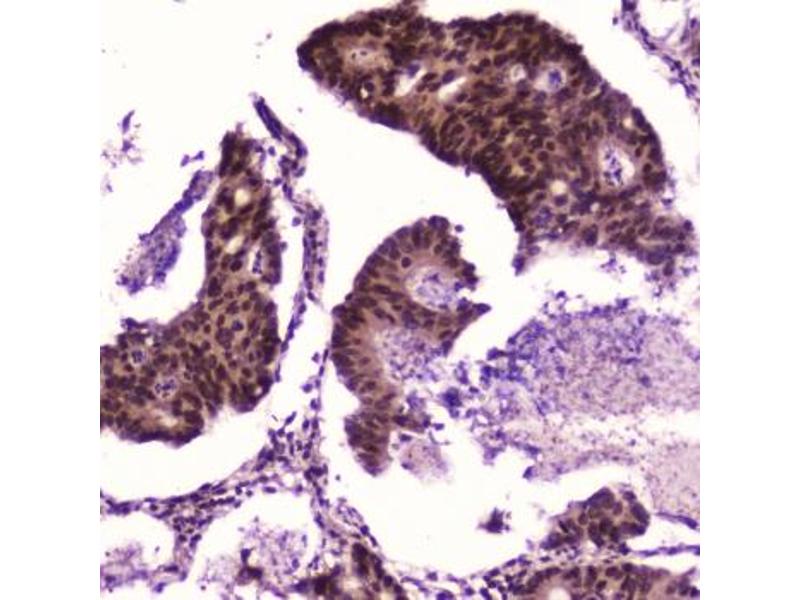

NFkBP65 适用: 人, 小鼠, 大鼠 WB, ELISA, IHC (p), FACS, IF (cc), IF (p), IHC (fro) 宿主: 兔 Polyclonal unconjugated

• Immunohistochemistry (IHC)

• Immunohistochemistry (Paraffin-embedded Sections) (IHC (p))

• Immunohistochemistry (Formalin-fixed Paraffin-embedded Sections) (IHC (fp))